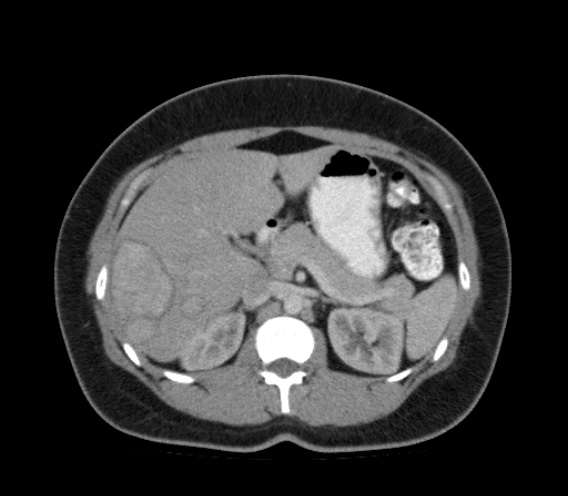

Paciente de 66 años con antecedente de pancreatitis, tomografía control.